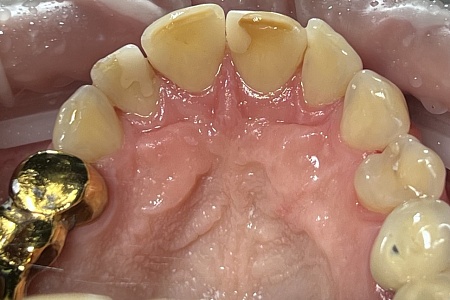

Работы наших врачей